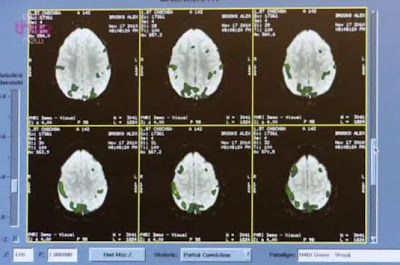

In a recently screened BBC documentary, UK neuroscientists suggested that the brains of Apple devotees are stimulated by Apple imagery in the same way that the brains of religious people are stimulated by religious imagery.

People have often talked about “the cult of Apple”, and if a recent BBC TV documentary is to be believed, there could be something in it.

The program, Secrets of the Superbrands, looks at why technology megabrands such as Apple, Facebook and Twitter have become so popular and such a big part of many people’s lives.

In the first episode, presenter Alex Riley decided to take a look at Apple. He wanted to discover what it is about the company that makes people so emotional. Footage of the opening of the Cupertino company’s Covent Garden store in central London last year showed hordes of Apple devotees lining up outside overnight, while the staff whipped up customers (and themselves) into something of an evangelical frenzy. This religious-like fervor got Riley thinking – he decided to take a closer look at the inside of the head of an Apple fanatic to see what on earth was going on in there.

Riley contacted the editor of World of Apple, Alex Brooks, an Apple worshipper who claims to think about Apple 24 hours a day, which is possibly 23 hours too many for most regular people. A team of neuroscientists studied Brooks’ brain while undergoing an MRI scan, to see how it reacted to images of Apple products and (heaven forbid) non-Apple products.

According to the neuroscientists, the scan revealed that there were marked differences in Brooks’ reactions to the different products. Previously, the scientists had studied the brains of those of religious faith, and they found that, as Riley puts it: “The Apple products are triggering the same bits of brain as religious imagery triggers in a person of faith.”

“This suggests that the big tech brands have harnessed, or exploit, the brain areas that have evolved to process religion,” one of the scientists says. A meeting with the Bishop of Buckingham, who reads the Bible using his Apple iPad, appeared to back up this assertion. He pointed out how the Apple store in, for example, Covent Garden has a lot of religious imagery built into it, with its stone floors, abundance of arches, and little altars (on which the products are displayed). And of course, the documentary doesn’t fail to give Steve Jobs a mention, calling him “the Messiah”.

Secrets of the Superbrands also looks at the likes of Facebook, which has enjoyed phenomenal success in just a few years. “Like Apple, mobile phones and social networks offer an opportunity for us to express our basic human need to communicate. And it’s by tapping into our basic needs, like gossip, religion or sex that these brands are taking over our world at such lightning speed,” Riley says. He concludes: “That’s not to say that clever marketing and brilliant technical innovation aren’t also crucial, but it seems that if you’re not providing a service which is of potential interest to every one of the 6.9 billion human beings on the planet, the chances are you’re never going to become a technology superbrand.”